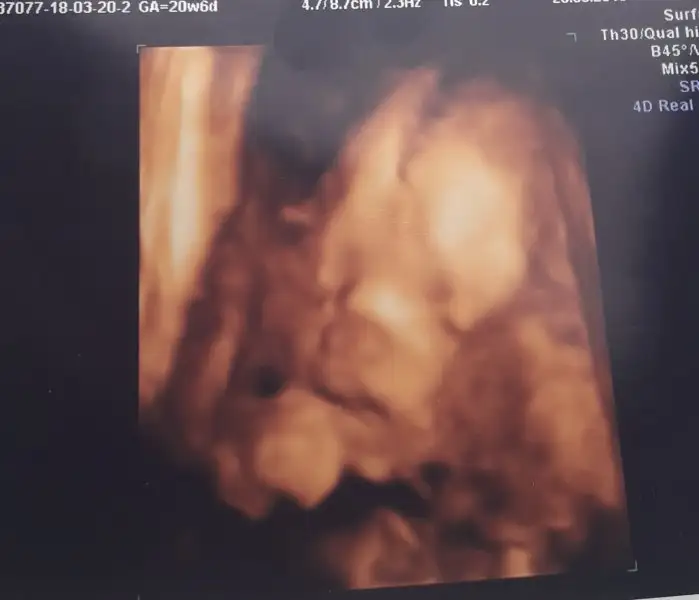

İşte benim melek kızım teyzeleri..

Eli çenesinde ne sıkıntı cikarsam diye düşünüyor..perinatoloji doktoru biraz korkuttu bizi ama onemli birsey degilmis şuan soyledikleri.kendi doktorumuz ferahlatti bizi.icimiz rahat buna şükür Rabbim evlatlarimizla sinamasin ins.